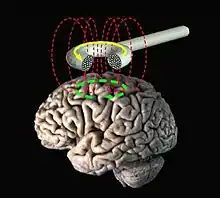

La stimulation magnétique transcrânienne (ou TMS, abréviation de l'anglais : Transcranial Magnetic Stimulation) est une technique médicale de stimulation transcrânienne utilisée dans le diagnostic et dans le traitement de certaines affections psychiatriques et neurologiques (il s'agit alors en général de rTMS repetitive Transcranial Magnetic Stimulation). C'est également un instrument de recherche en neurosciences.

La stimulation magnétique transcrânienne consiste à appliquer une impulsion magnétique sur le cortex cérébral à travers le crâne de façon indolore au moyen d'une bobine. Conformément à la loi de Lenz-Faraday, la variation rapide du flux magnétique induit un champ électrique qui modifie l'activité des neurones situés dans le champ magnétique. À partir d’un certain seuil d’intensité, la modification rapide du champ magnétique induit localement une dépolarisation neuronale (potentiel d’action), laquelle se propage le long des axones, puis de proche en proche par l’intermédiaire des synapses, en s’atténuant avec la distance.